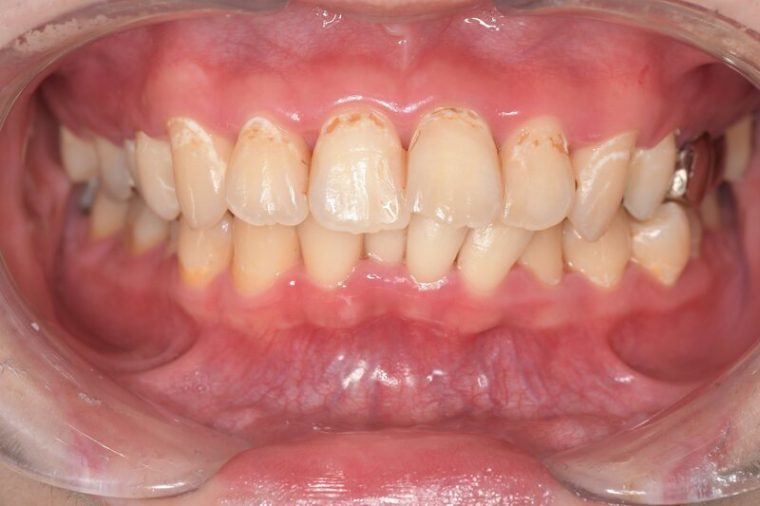

CASE 3

Before

After

基本情報

| 年齢・性別 | 30代・女性 |

|---|---|

| 主訴 | 定期検診 |

| 治療内容 | PMTC |

| 治療期間 | 60分 |

| 治療費 | 5,750円 |

| リスク・副作用 | しみる可能性があります。 |

| 治療方針 | PMTCでステインの除去。 |

| 担当者所見 | ステインが付きやすいため、3カ月毎の定期検診で除去する。 |